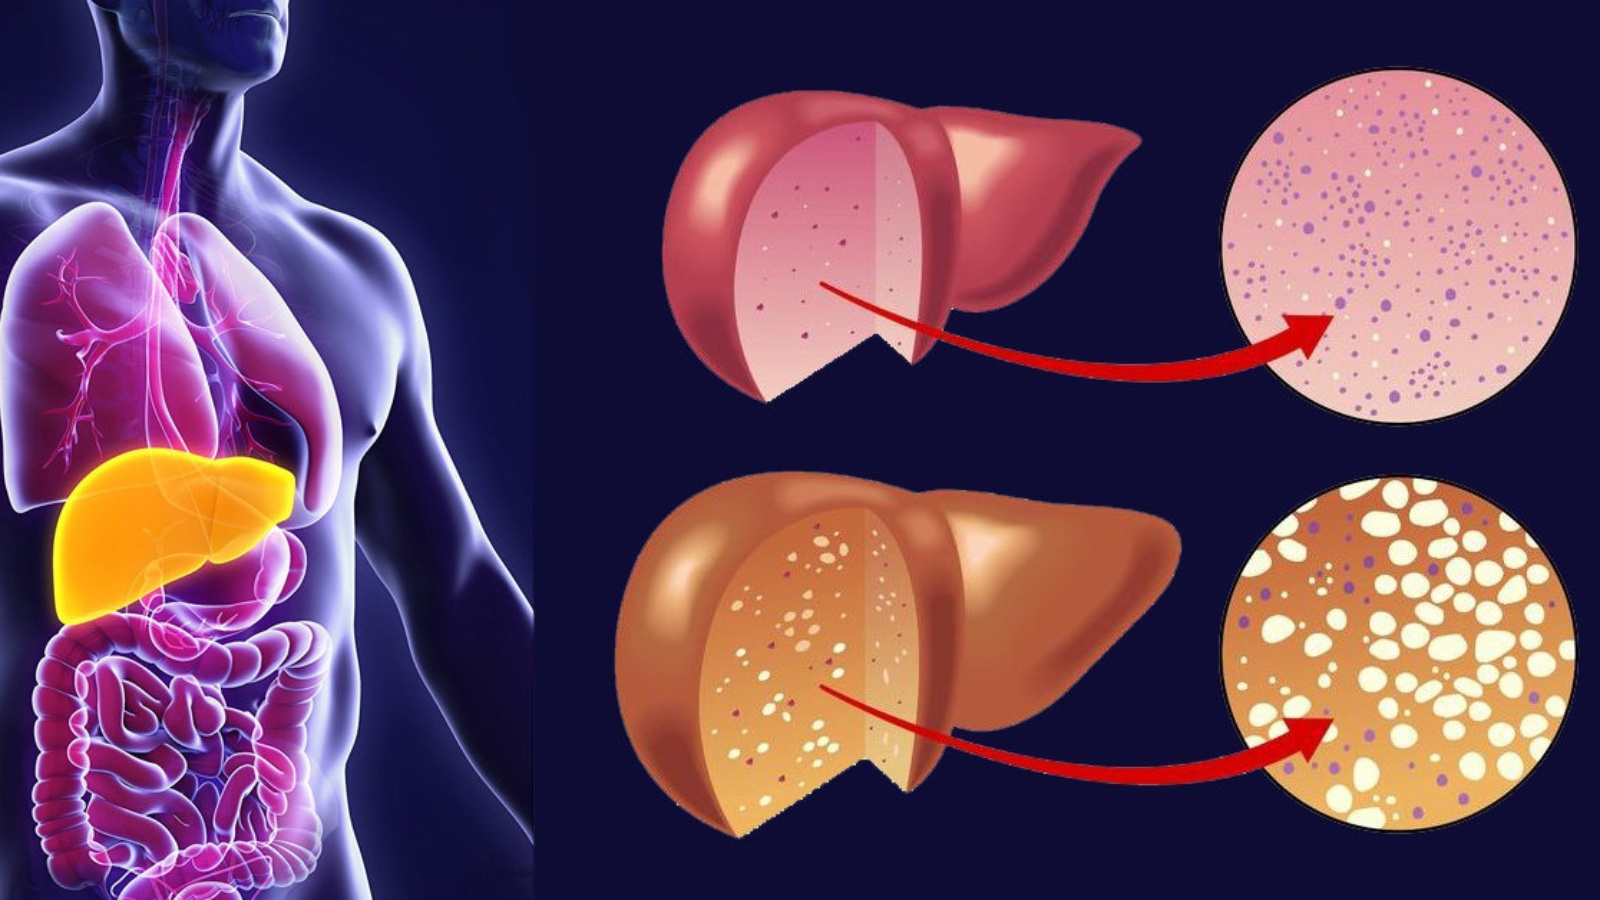

Практические советы по лечению ожирения печени в домашних условиях

Узнайте, как можно эффективно и безопасно лечить ожирение печени в домашних условиях с помощью простых рекомендаций и советов. Избавьтесь от этого заболевания и улучшите свое здоровье с легкостью.

Избегайте переедания и контролируйте свой вес. Жирное скопление в организме может наносить вред печени и ухудшать ее функции.